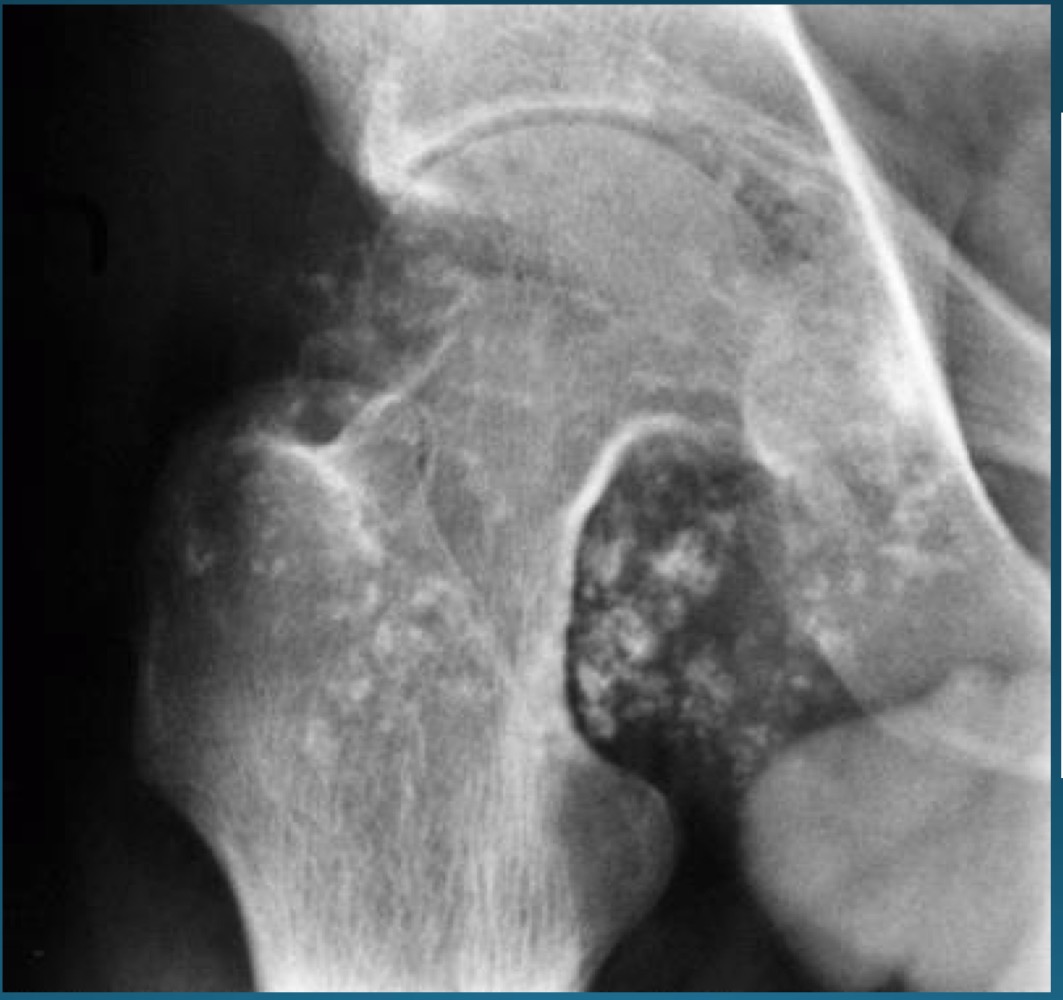

what is this finding?

synovial chondromatosis (SCM)

what is the most commong site for synovical chrondomatosis

knee